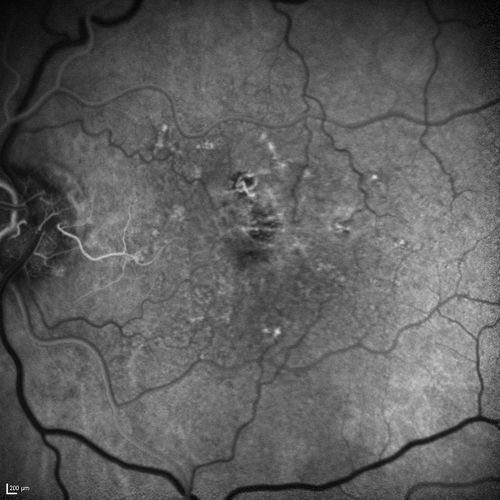

Dry AMD - Confluent Drusen Sparing Center of Macula which has Atrophy

65 year old woman, VA 20/40 OD; 20/80 OS. The center of the macula has few or no drusen with predominantly non-geographic atrophy